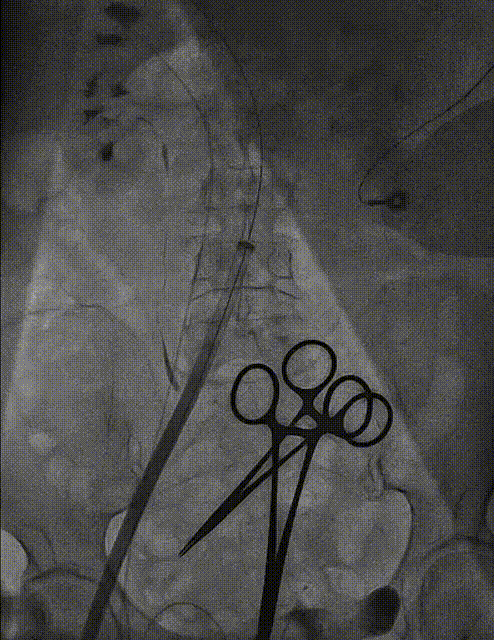

宋光远教授 首都医科大学附属北京安贞医院(点击查看专家详细简历) 技术革新不止,创新求索不辍:一切从患者出发,不断追求创新是内心的坚定。当年‘ALL IN ONE’的探索,正是怀揣着这份初心 —— 通过整合器械与操作,将入路创伤缩至最小,让患者在微创中更快康复,这是技术对患者的温柔承诺。而术中脑保护,是我们为安全筑牢的另一道防线。 此次预装干瓣的临床应用,让我们直面瓣膜“耐久性“临床困境,期待创新技术助力全生命周期管理! 病例概览 患者病史 患者因 “劳力性呼吸困难半年余,加重 20 天” 入院。高血压病史 20 年,最高血压 160/110mmHg;高脂血症病史;反流性食管炎。 超声提示:主动脉流速 Vmax 4.66 m/s,平均压差 53mmHg,左室射血分数(LVEF)40%; 超声诊断:主动脉瓣狭窄(重度)、主动脉瓣反流(轻中度)、二尖瓣狭窄(轻度)、二尖瓣反流(轻度)、三尖瓣反流(轻中度)、左房增大,左室肥厚。 术前CT 瓣环(Annulus)直径:22.9mm,左室流出道(LVOT)直径:周长径 23.8mm;总钙化负荷1239mm³(HU850),钙化集中于无冠窦,且蔓延至 LVOT,呈重度钙化表现;LVOT-Annulus 呈微直筒型,瓣上限制较重。左冠脉开口高度略低,瓣叶不长、窦部空间较大,结合钙化分部情况,预估双侧冠脉遮挡风险较低。室间隔膜部较短(2.4mm)有一定PPI风险,心室大小可,心脏角度64°,升主长度短于胶囊腔长度,同轴有一定困难。 · 造影角度及入路情况:主动脉弓角度可,但降主动脉折曲明显,双侧髂股动脉存在粥样硬化。 手术策略 采用 “极简式” 手术方案:18/20mm 球囊预扩张,植入金仕生物 Prostyle-A 预装干瓣(AV 26),配合长鞘,同时植入脑保护装置以降低卒中风险。 手术过程 球囊预扩:18号球囊预扩 输送系统顺利过弓跨瓣: 瓣膜植入:工作位观察位置适宜,完成植入。 术后即刻:术后造影显示瓣膜位置佳 入路与血管:撤出大鞘后检查,降主动脉仍存在较大弯折;入路闭合良好,无明显出血或血管并发症。 Prostyle A®预装干瓣——助力临床最优化解决方案: √ Mircro-EX™专利抗钙化技术:极简式预装干瓣,不使用戊二醛浸泡,减少钙化成因,干态存储的瓣膜术中无需清洗瓣膜,减少组装步骤,缩短手术时间,尤其适合复杂病例中的高效操作; √ 平衡的径向支撑力:重度钙化的患者,形态展开良好,在横位心等复杂情况下实现稳定锚定及释放; 专家简介 苑飞 首都医科大学附属北京安贞医院(点击查看专家详细简历) 姚晶 首都医科大学附属北京安贞医院(点击查看专家详细简历) · END ·